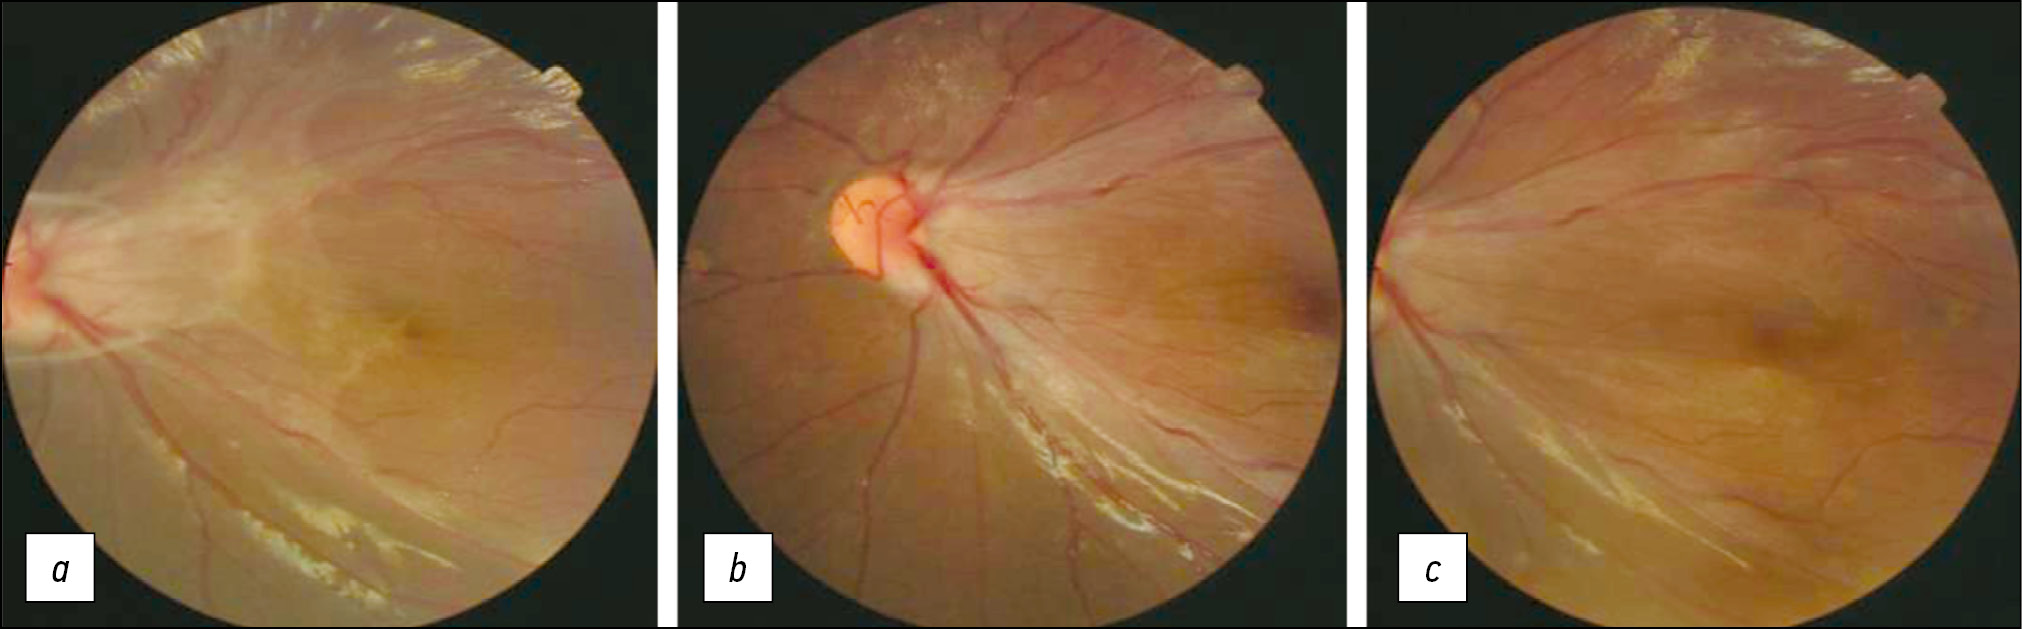

У всех пациентов достигнуто уменьшение тракции сетчатки в макуле, у четырёх детей наблюдалось повышение максимальной корригированной остроты зрения (МКОЗ), у одного ребенка — острота зрения не изменилась. У четырёх детей, наблюдавшихся в динамике, через 6–7 месяцев состояние глаз оставалось стабильным (рис. 1).

Рис. 1. Пациент Г., семейная экссудативная витреоретинопатия стадии 2А, эпиретинальная мембрана в области заднего полюса: a–c — до операции, центральная толщина сетчатки (ЦТС) 733 мкм, максимальная корригированная острота зрения (МКОЗ) 0,1; d–f — после операции: ЦТС 354 мкм, МКОЗ 0,8; a, d — фотография глазного дна; b, e — оптическая когерентная томография (ОКТ) диска зрительноно нерва; c, f — ОКТ макулярной зоны.

В результате первичного вмешательства во всех случаях достигнуто снижение тракции сетчатки в центральном отделе (рис. 3), закрытие макулярного разрыва, неполное прилегание сетчатки в 6 глазах, полное — в 2 глазах. Повышение МКОЗ после операции наблюдалось в 3 случаях, в 5 случаях острота зрения не изменилась.

Рис. 3. Пациентка А., семейная экссудативная витреоретинопатия стадии 3Б, фотография глазного дна: а — до операции, эпиретинальные мембраны в области заднего полюса с тракцией; b, c — после операции, уменьшение тракции в области заднего полюса, максимальная корригированная острота зрения 0,3–0,4 (не изменилась).

Рис. 4. Пациентка Л., семейная экссудативная витреоретинопатия стадии 3Б, фотографии глазного дна: а — сразу после операции: уменьшение тракции в заднем полюсе, высоты и площади отслойки сетчатки, увеличение максимальная корригированная острота зрения (МКОЗ) с 0,01 до 0,05; b — через год, рассасывание субретинального экссудата, МКОЗ 0,03.